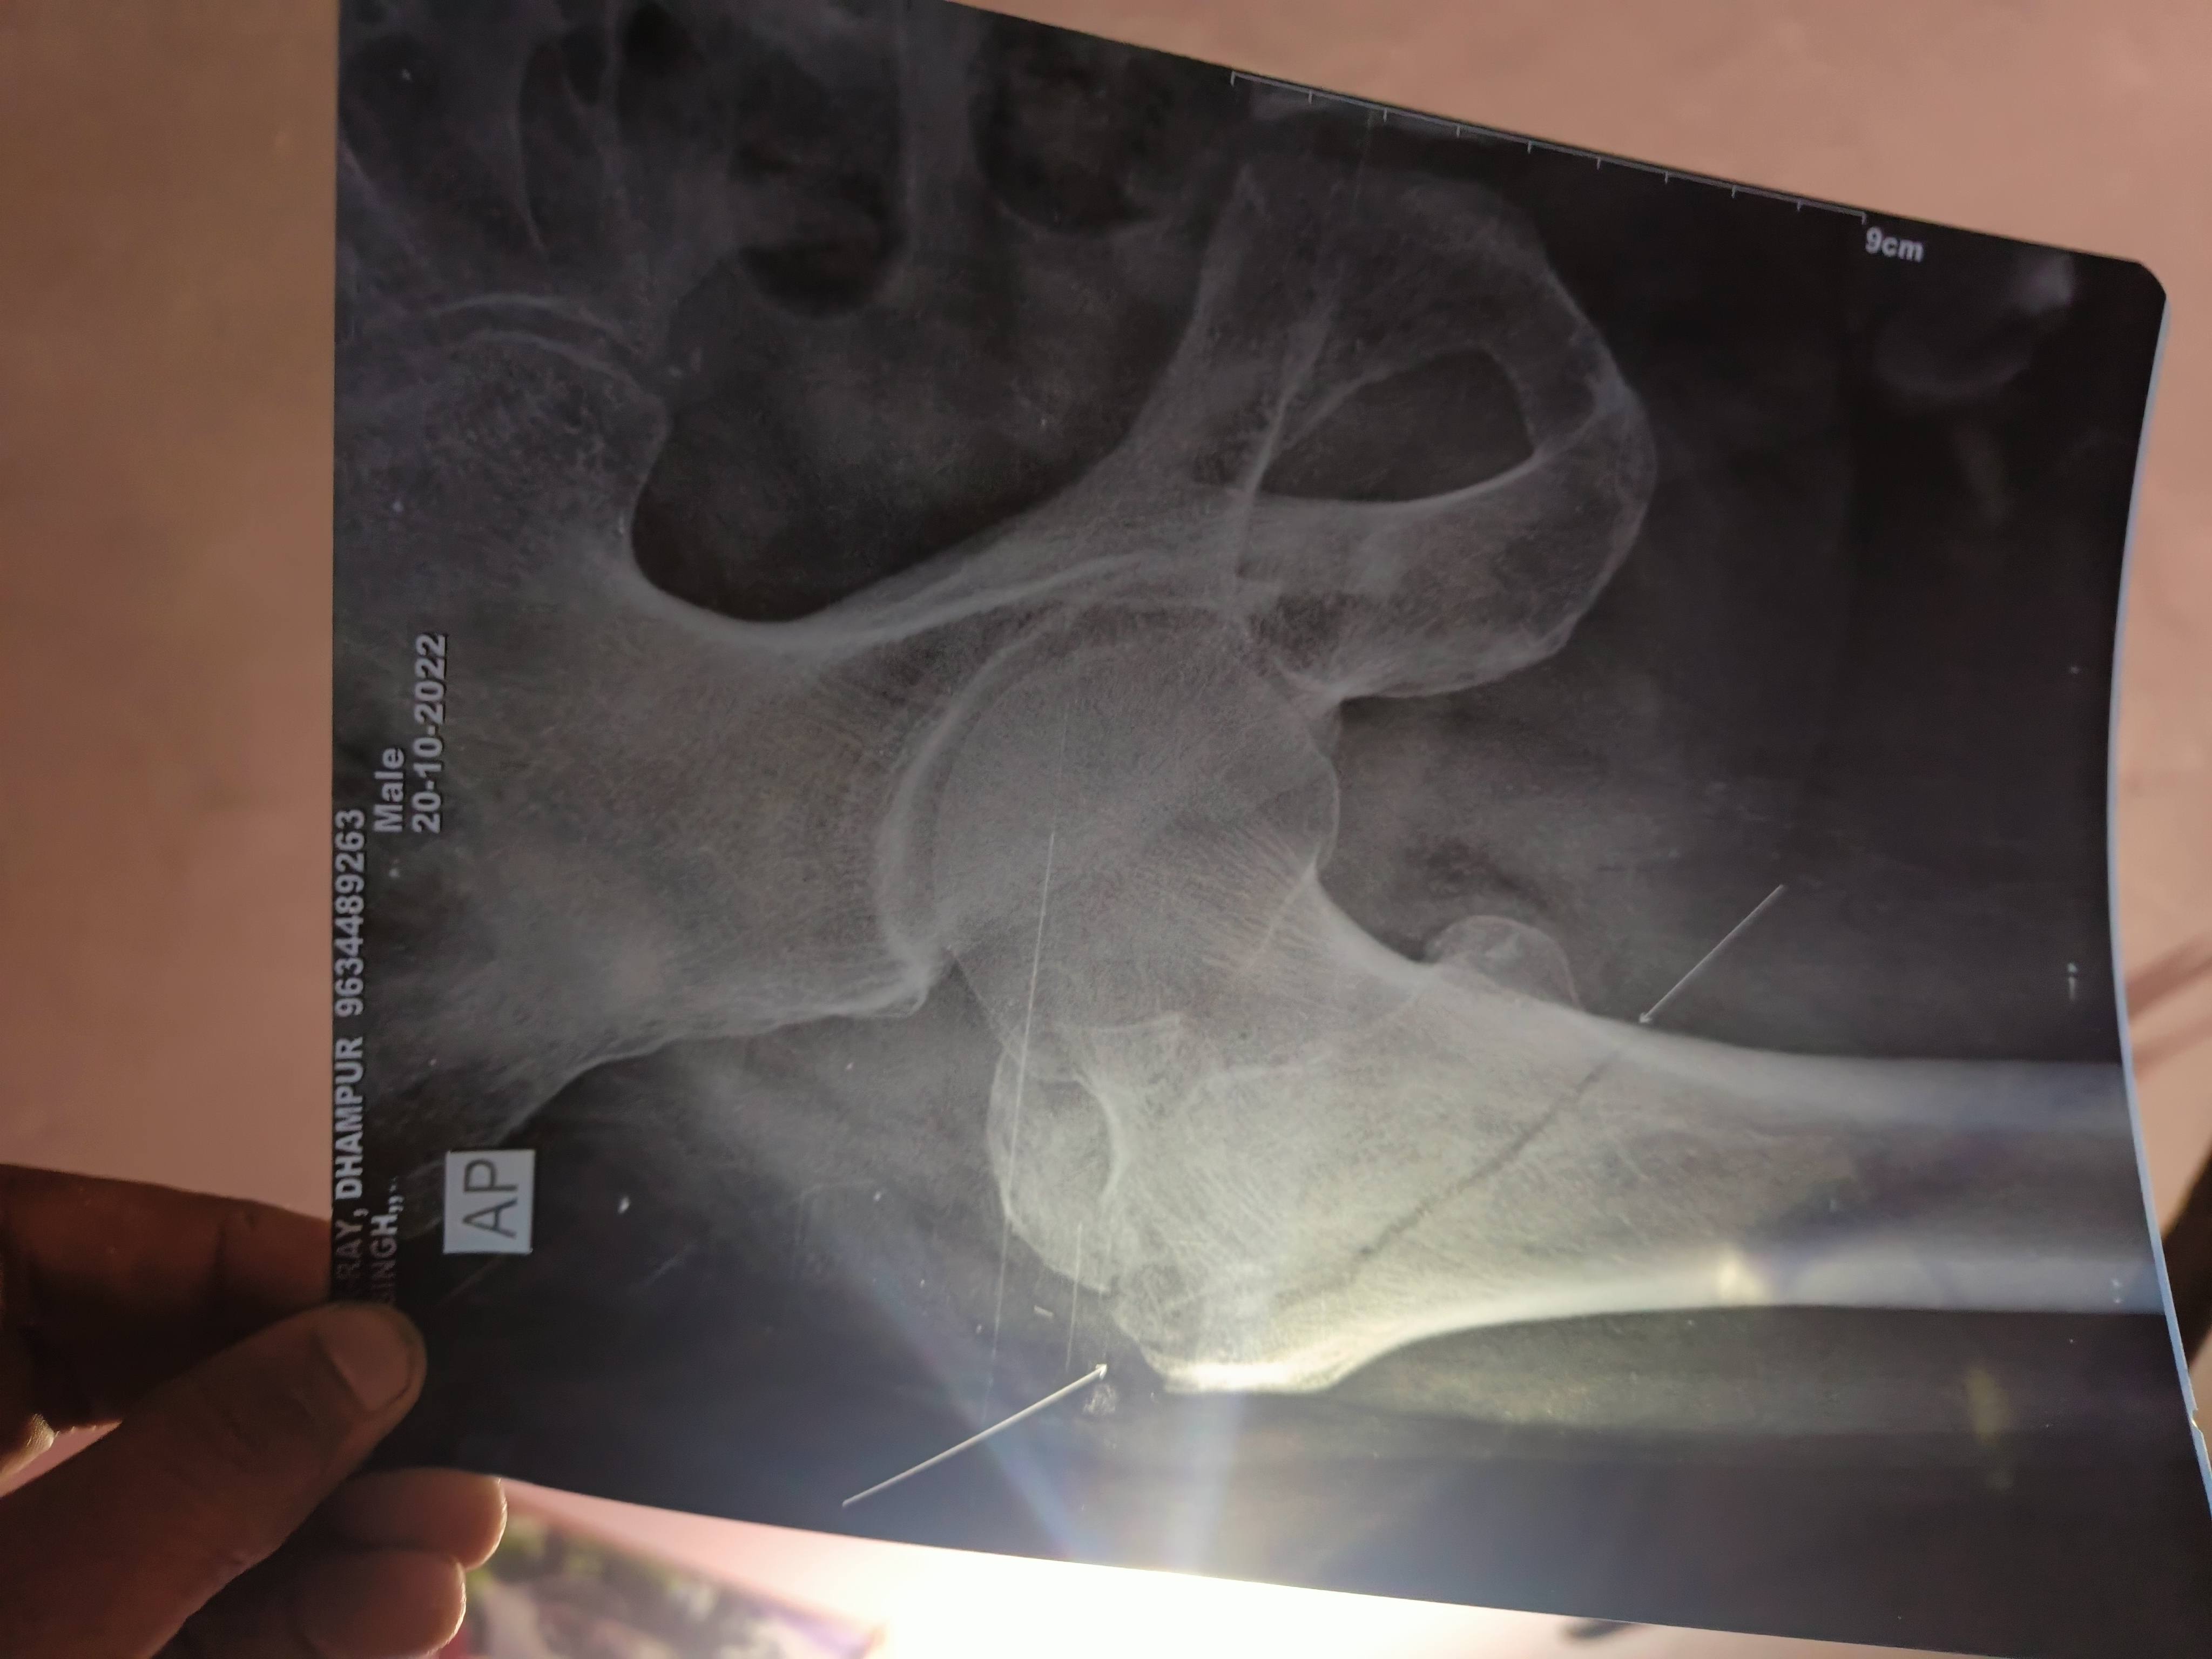

Sumit Yadav

Bone Fracture

Sir mere pati 2 mahine pahle sidi se gir gye the bahut ijjal karwaya magar abhi tak thik nhi hua hai wo thik se chal fir bhi nhi pa rhe hai bilkul kamar ke niche dono side gilti type ka ho gya hai ya nas ka problem hai samjh me nhi aa rha hai aur kuch din se wo bol rhe hai ki mere sarir ke sare hadiyo me dard suru ho gya hai rat ko dard pet tak aa jata hai please sir kuch help kijiye?